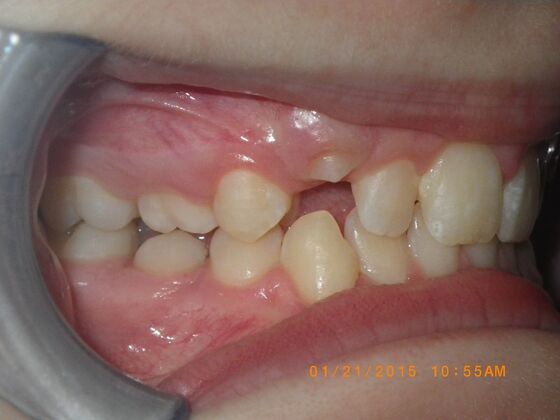

Orthodontics: Case 10

Description

This case presents with a dental midline discrepancy. The upper incisors are tipped toward the palate, which prevents the lower incisors from establishing proper arch form. The upper right molar has drifted forward, causing the upper midline to be skewed to her left. By distalizing the upper left molar, we can correct the midline discrepancy. Lastly, both upper and lower arches need expansion. All of this was completed with conventional straight wire appliances within 2 years.